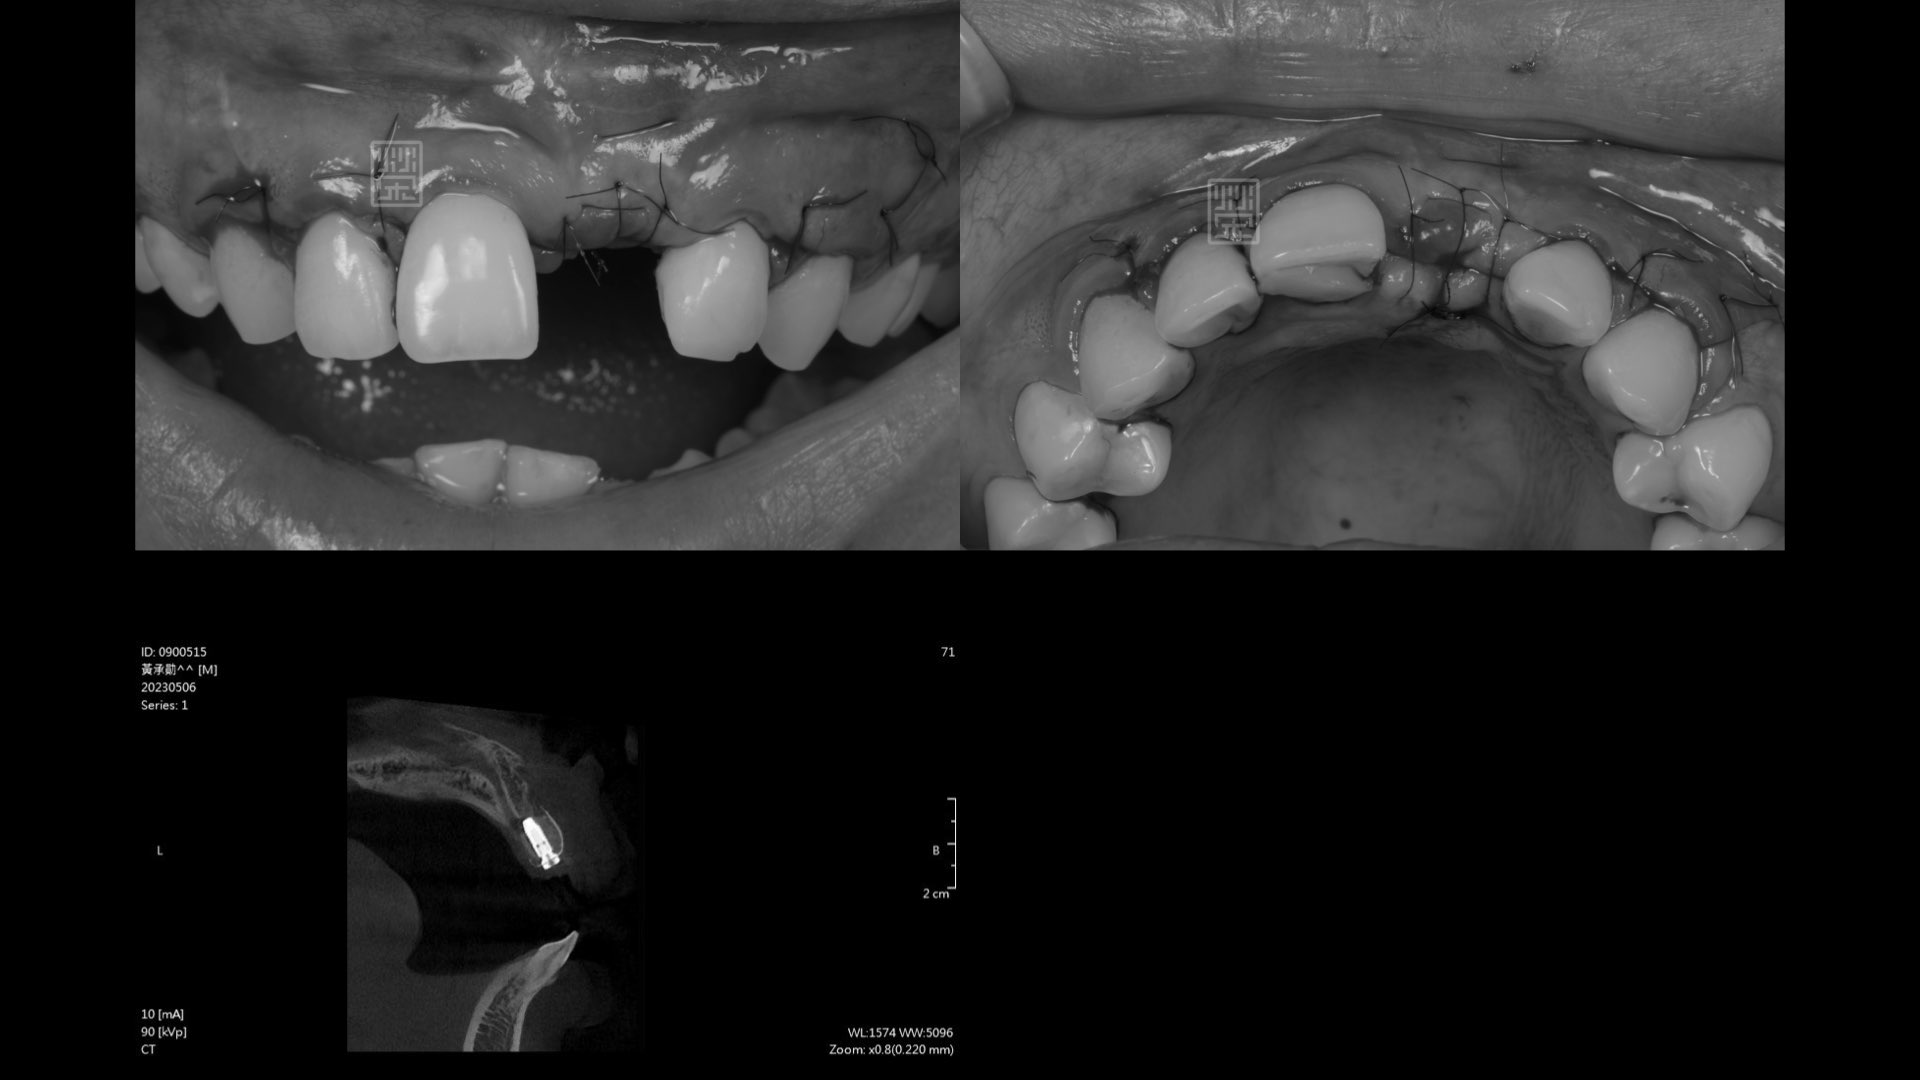

接出植牙支台

牙齦軟組織重建

植牙臨時假牙